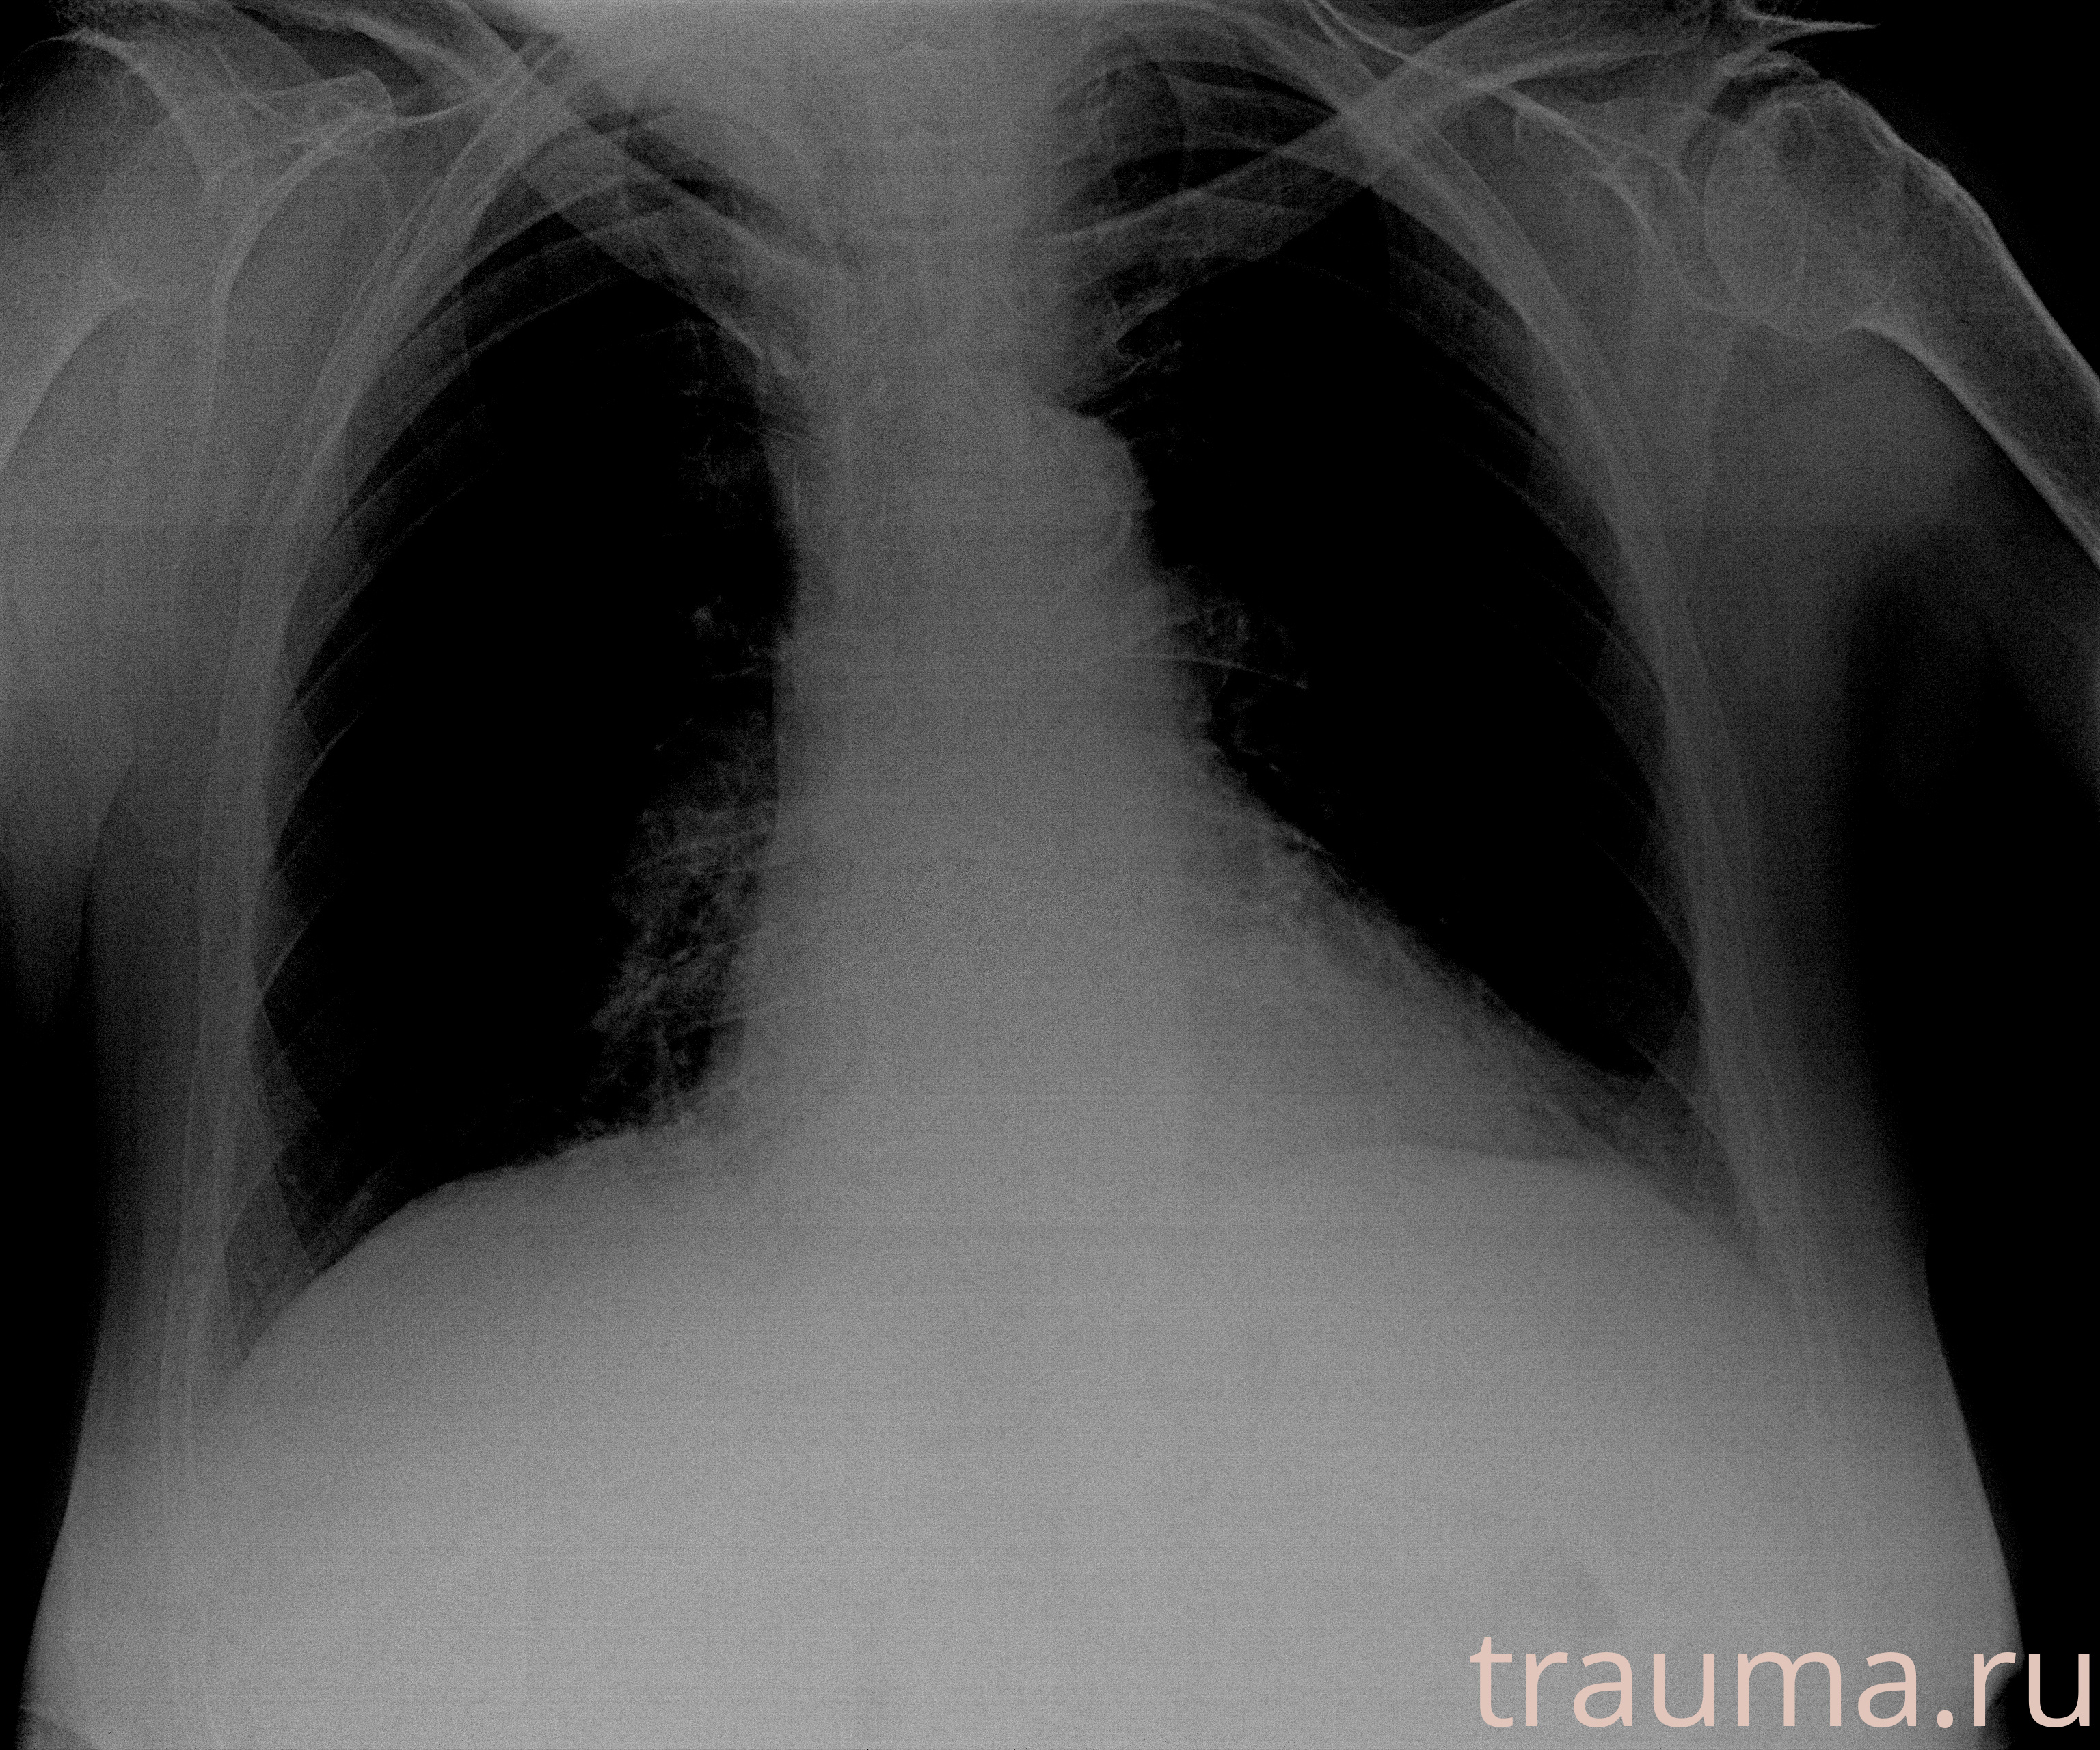

Рентген на дому: по вашему адресу приезжает врач-рентгенолог, травматолог-ортопед с мобильным рентгеновским аппаратом, проводит диагностику травмы или заболевания, делает необходимые рентгенограммы, дает рекомендации по дальнейшему лечению. Получить качественные снимки в домашних условиях возможно благодаря уникальной методике, разработанной МосРентген Центром для института  Склифосовского

при переломе шейки бедра и пневмонии от компании МосРентген Центр - партнера Института имени Склифосовского